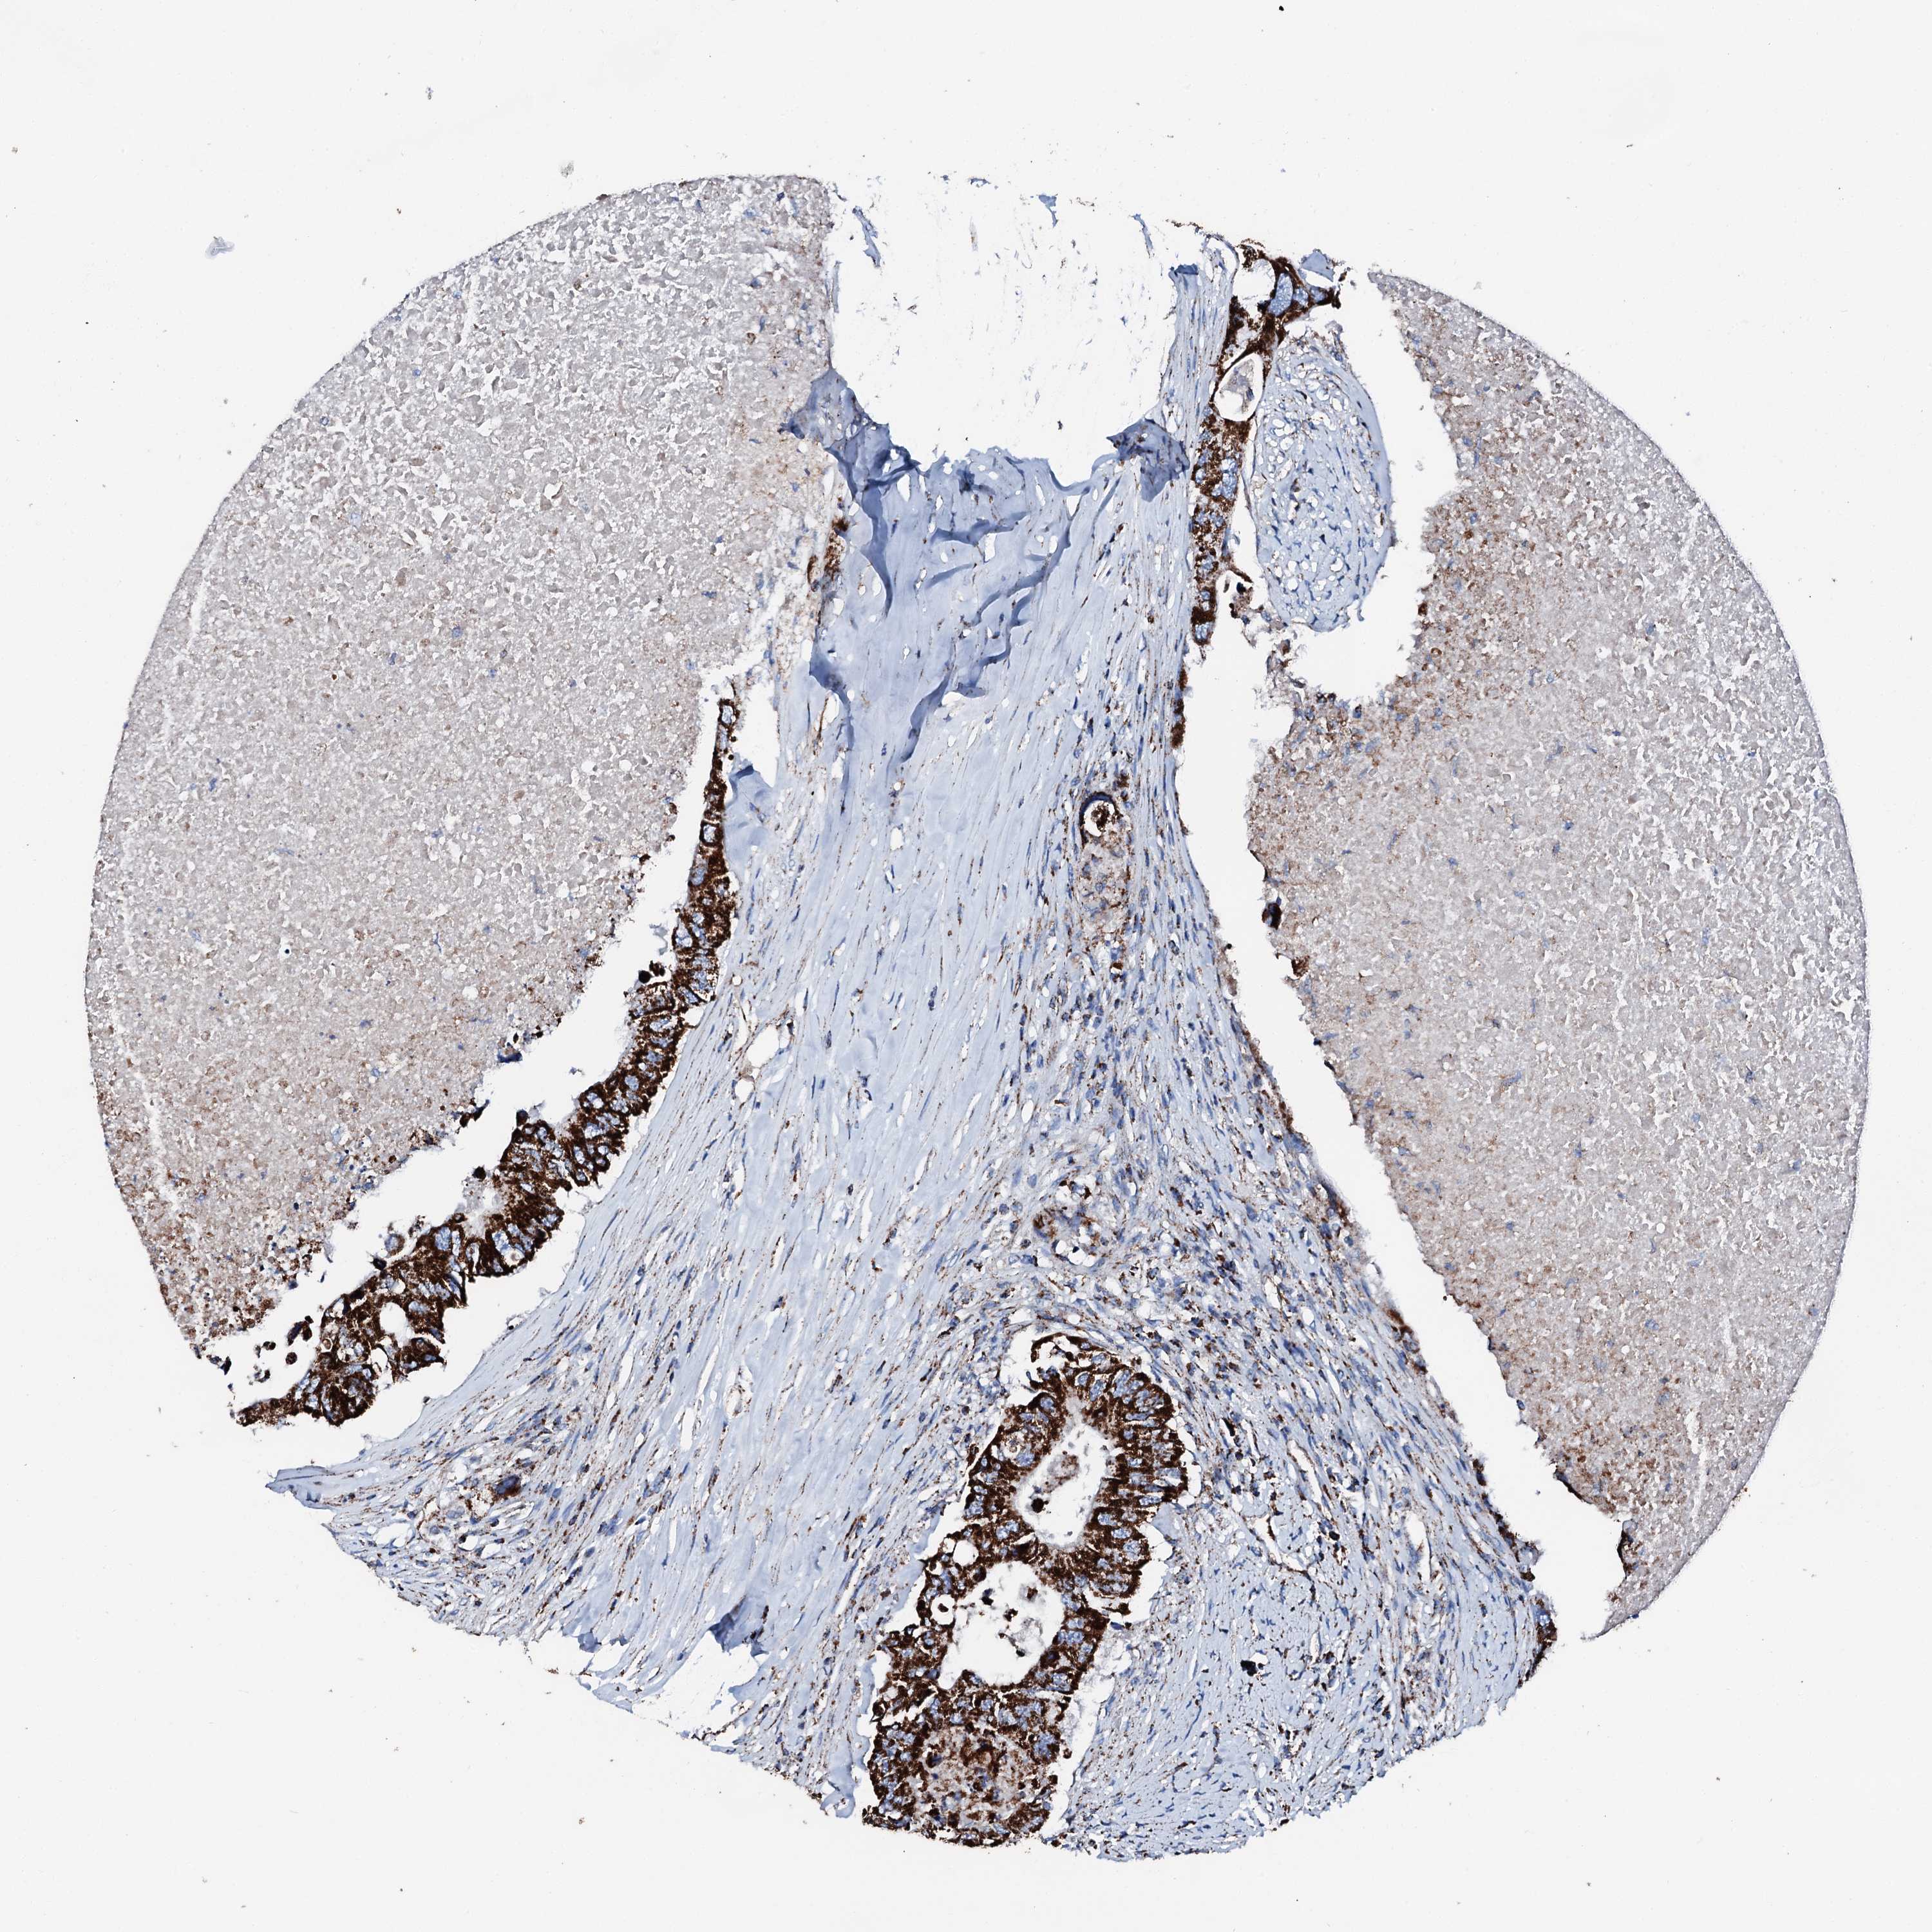

CANCER COLORECTAL CANCER Show tissue menu

Colorectal cancer

Human cancer

Colon adenocarcinoma

Rectum adenocarcinoma